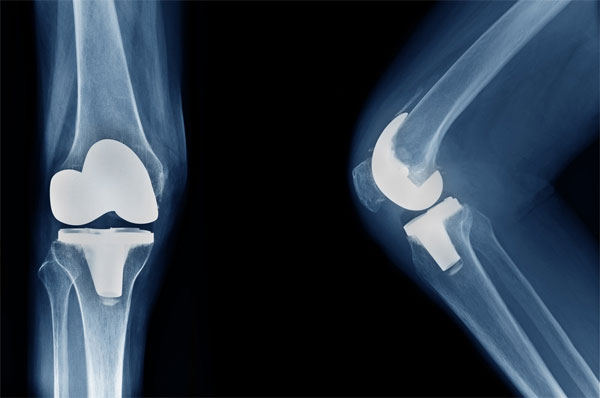

Revision arthroplasty — a surgery performed when an artificial hip or knee joint wears out, loosens, or fails — is becoming more common as implants installed 15–20 years ago begin to reach the end of their lifespan. Artificial joints typically last only 20–25 years, making wear and tear inevitable.

Experts at the three-day Revision Arthroplasty Conference (RAC) 2025 stressed that revision surgeries are significantly more demanding than primary joint replacements. Unlike initial procedures, revision surgeries involve removing an existing implant — often associated with bone loss — and require advanced techniques, detailed planning, and extensive experience.

He highlighted that revision cases demand advanced implants, sophisticated tools, and the ability to manage complications such as aseptic loosening, implant wear, infections, periprosthetic fractures, and joint instability.